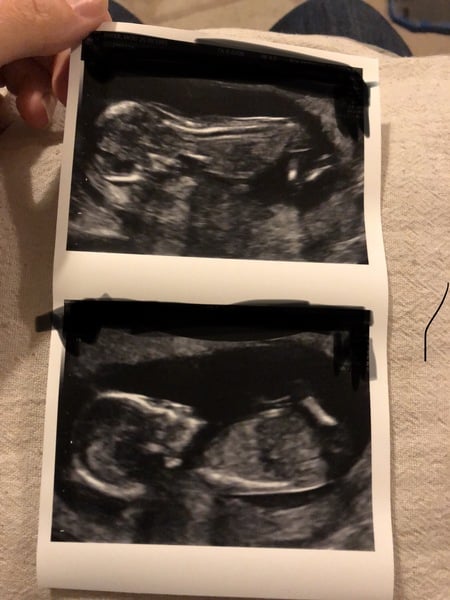

lolacola13 · 25/09/2018 23:54

Aloha just wondering if anyone is any good at looking at scans I'm 11 weeks and wondering where the placenta is forming here in this pic . Just curious! Thanks xoxoxox

We had our scan yesterday which put me a whole week ahead of where I should be, so I’ve now skipped week 13 totally which is a little strange and am now 13.5. I’m pretty sure my dates were right, especially as we had scans at 6 and 9 weeks, and now I’m worried as clearly this baby is going to take after dh and be a giant! Baby was not playing ball and I had to jiggle as if my life depended on it, but it would not budge, hence the picture of it essentially lying on its tummy looking like it’s crawling. It’s arms and legs look so long compared to 3 weeks ago, it really is extraordinary. I need to try and learn to relax now. My colposcopy showed no problem with my cervix, and the sonographer seemed happy with the unchallenged measurement of 2.2. Anyone care to have a stab at the nub for me if the picture isn’t too bad? I have no idea what I’m looking for!